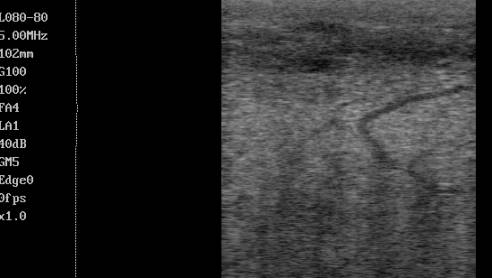

данных и последующая обработка эхограмм показали, что ультрасонографически

текстура паренхимы здоровой молочной железы лактирующей коровы имеет

гипоэхогенную однородную структуру. Кровеносные сосуды и молочные ходы

идентифицируются в виде анэхогенных каналов, как в продольном, так и в

поперечном сечении. Молочные ходы, в отличие от кровеносных сосудов, не имеют

выраженных эхогенных стенок и отличаются более искривленными траекториями (рис.

1).

Рисунок 1 – Эхограмма паренхимы молочной железы

здоровой коровы.